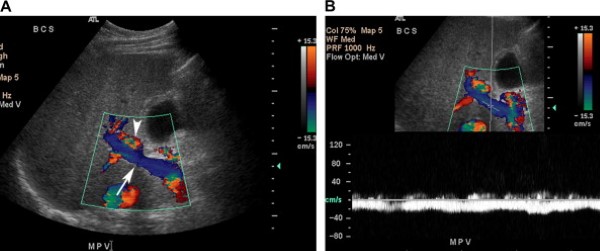

Tĩnh mạch cửa được tạo thành do hợp nhất tĩnh mạch lách với tĩnh mạch mạc treo tràng trên và mang máu từ ruột, tụy, lách tới gan (Hình 1). Các ngành phải và trái của nó tách ra ở cửa gan, sát với động mạch gan và ống gan chung. Tĩnh mạch cửa và các nhánh trong gan có thành mỏng, hơi tăng âm, và dòng chảy trong hệ thống tĩnh mạch cửa luôn hướng vào gan. Với các mặt cắt liên sườn hoặc dưới sườn, dòng máu trong tĩnh mạch cửa và ngành trái hướng tới đầu dò, và dòng chảy ở ngành phải đi xa đầu dò.

Phổ Doppler biểu hiện sóng một pha hầu như không biến đổi theo hô hấp (Hình 2). Tốc độ trung bình trong tĩnh mạch cửa từ 13 tới 23 cm/s khi nhịn đói [2].

Hình 2. Tĩnh mạch cửa bình thường ở bệnh nhân nam 48 tuổi có tiền sử HIV và xuất huyết tiêu hóa thấp. (Hình A) Ảnh thang xám cho thấy tĩnh mạch cửa bình thường chia thành ngành phải và trái đi vào gan, tĩnh mạch có thành tăng âm và trong lòng mạch có các chấm đậm âm nhỏ. (Hình B) Ảnh siêu âm duplex Doppler và màu cho thấy dòng chảy tĩnh mạch cửa về gan với sóng tĩnh mạch dạng một thì (pha) thay đổi rất ít theo hô hấp. Dòng máu trong tĩnh mạch cửa và ngành trái hướng tới đầu dò (màu đỏ). Ở ngành phải tĩnh mạch cửa, dòng máu chảy xa đầu dò (màu xanh). Tốc độ trung bình 35 cm/s. Lưu ý bệnh nhân có nhiều dịch ổ bụng.